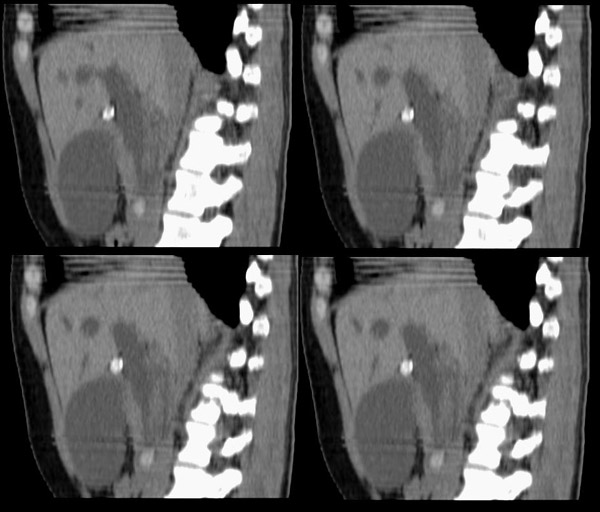

腹部ct平扫:(5mm层厚)

f42y近半月来无明显诱因出现右上腹疼痛之主诉就诊。疼痛多于饭后半小时发作,为持续性隐疼,呈阵发性、刀割样、钻顶样疼痛加剧,且向右肩背部放射,伴恶心、出汗、呕吐,呕吐内容物为胃内容物,无呕血,时有返酸、呃逆、烧心感,无腹胀、腹泻及黑便。时有发冷、发热(但体温不高);呕吐后腹疼稍有缓解,在当地诊所按“胃炎”对症治疗10天,效果不佳。血常规为:白细胞:9、8*109,中性64%,血红蛋白为151g/l,血小板为167*107。 既往有胆道蛔虫病史30余年,曾有呕虫史,否认肝炎及肺结核、溃疡病史。无外伤、手术及药物过敏史,陕西丹凤县四坪镇人,未去过疫区。

整个胆道系统内可见多发蛔虫钙化改变,胆道扩张.

行胆囊切除术及胆总管探查术:探查见肝脏大小正常,肝缘稍钝,肝表面光整,胆囊大小12*3*3cm3,壁水肿增厚约0。5cm,张力稍高,胆囊与大网膜呈纤维粘连;胆总管宽约2cm,壁明显增厚,触摸胆总管,隐约可触及一条状物,于胆总管做一长约1、5cm的纵行切口,用取石钳在胆总管内取出一条长约16cm长黑色的长条状物,较脆易折断,宽约0、6cm,证实为蛔虫尸体。用探子往下探,未发现下端结石最后诊断:胆道蛔虫症继发胆系梗阻性扩张。